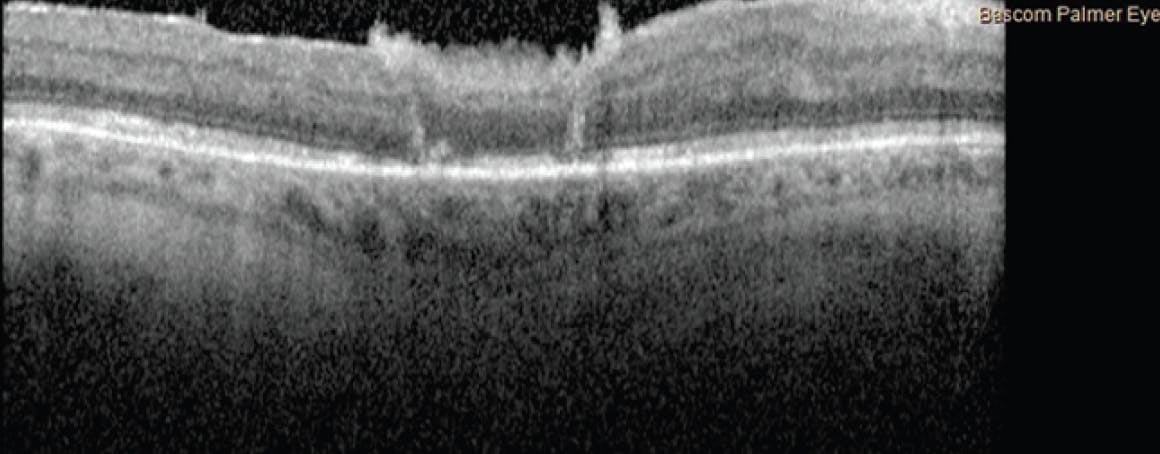

The patient presented here elected to undergo ART for refractory primary FTMH. He failed to position as instructed, and on postoperative day 1, the patient had a VA of 20/250 with a dislocated graft and a persistent FTMH (Figure 2).

<p>Figure 2. The postoperative day 1 OCT scan showed the FTMH without anatomic closure.</p>

Figure 2. The postoperative day 1 OCT scan showed the FTMH without anatomic closure.